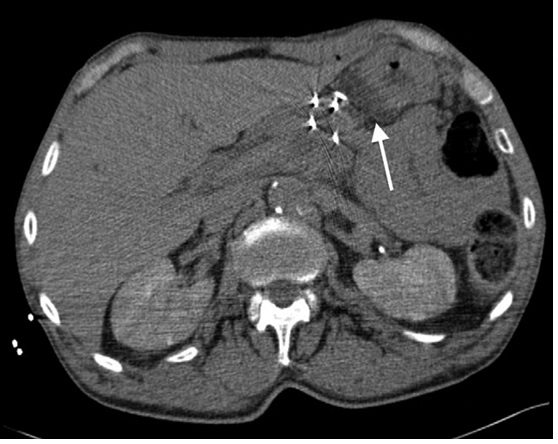

经皮消融计划和实行两次消融会话来避免一次使用多于六根探针。病人全身麻醉后,4个15cm的单极探针,纳米刀Nanoknife; AngioDynamics, Latham, New York 在方形配置平均1.8cm间距的超声波指引下放置在肿瘤的中央和侧面。带有造影剂的CT影像用来评估相应血管的探针位置和探针距离。(图2)。所有探针有1cm的电极接触其中一个探针用的是经肝途径。一个22Ga脊椎穿刺针(Becton Dickinson, Franklin Lakes, New Jersey) 在US指引下放置在胃肝处来分离无菌水。

图2:IRE针放置的位置